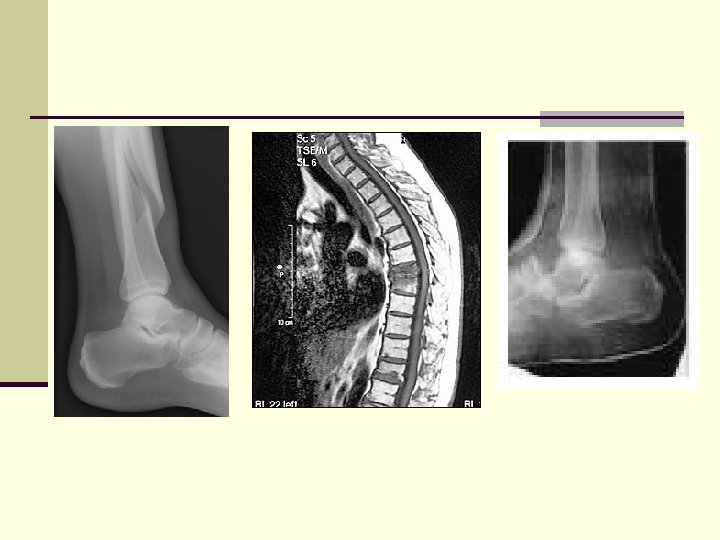

Fractures n A fracture is a break in a bone. n Fractures are classified according to their external appearance, the sit of the fracture, and the nature of the break in the bone. Some fractures fall into more than one category.

Types of Fractures n Spiral – a fracture produced by twisting stresses, spread along the length of the bone n Compression – a fracture occurring in vertebrae subjected to extreme stresses, as when landed on your seat after a fall n Pott’s fracture –occurs at the distal end of the fibula usually from an eversion ankle sprain

Fracture Treatment n If a fracture is suspected, appropriate splinting and referral for an x-ray should be accomplished.